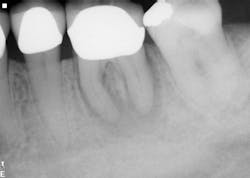

The first case involves a 49-year-old female. Tooth no. 31 had a deep periodontal probing on the straight buccal. The patient was warned that the tooth might be fractured, but she still decided on treatment (figure 1).

Calcium hydroxide paste medication was placed in the canals on three visits, each two weeks apart. Treatment included a total of six weeks of calcium hydroxide therapy.